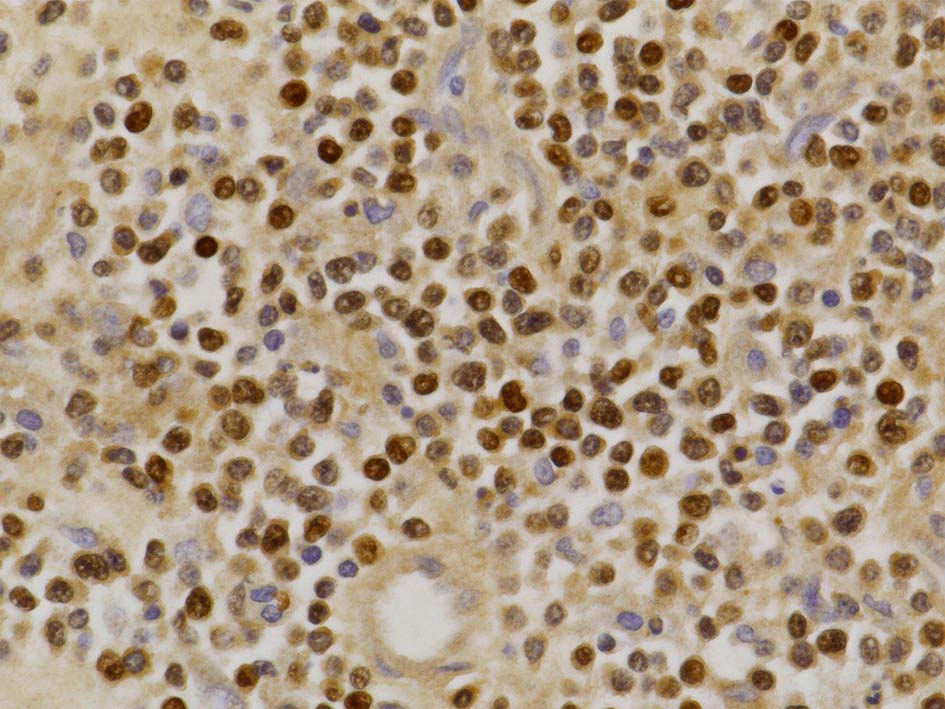

免疫染色

病理診断: Extranodal NK/T-cell lymphoma, nasal type of the testis